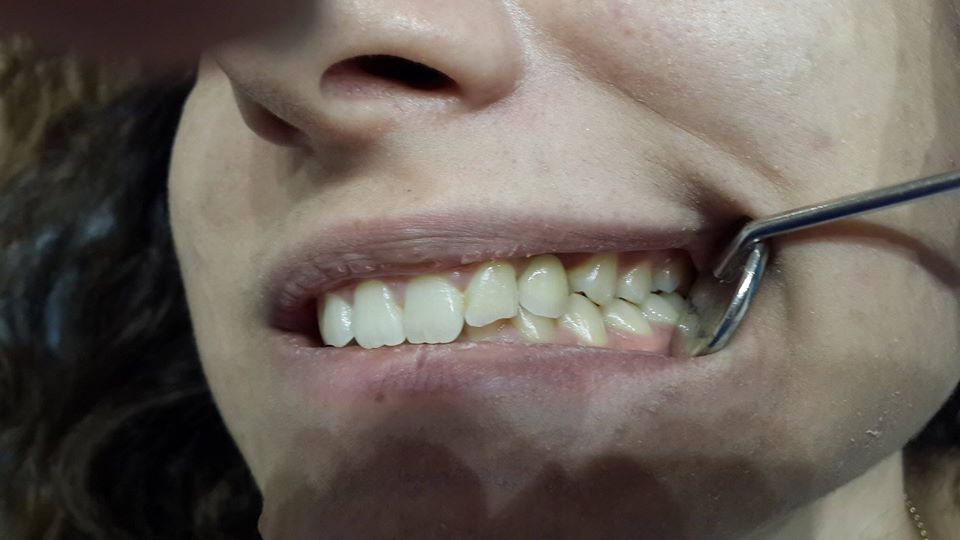

Canine restoration using implantation

To successfully restore the canine, the patient was simultaneously removed a tooth and used bone material.